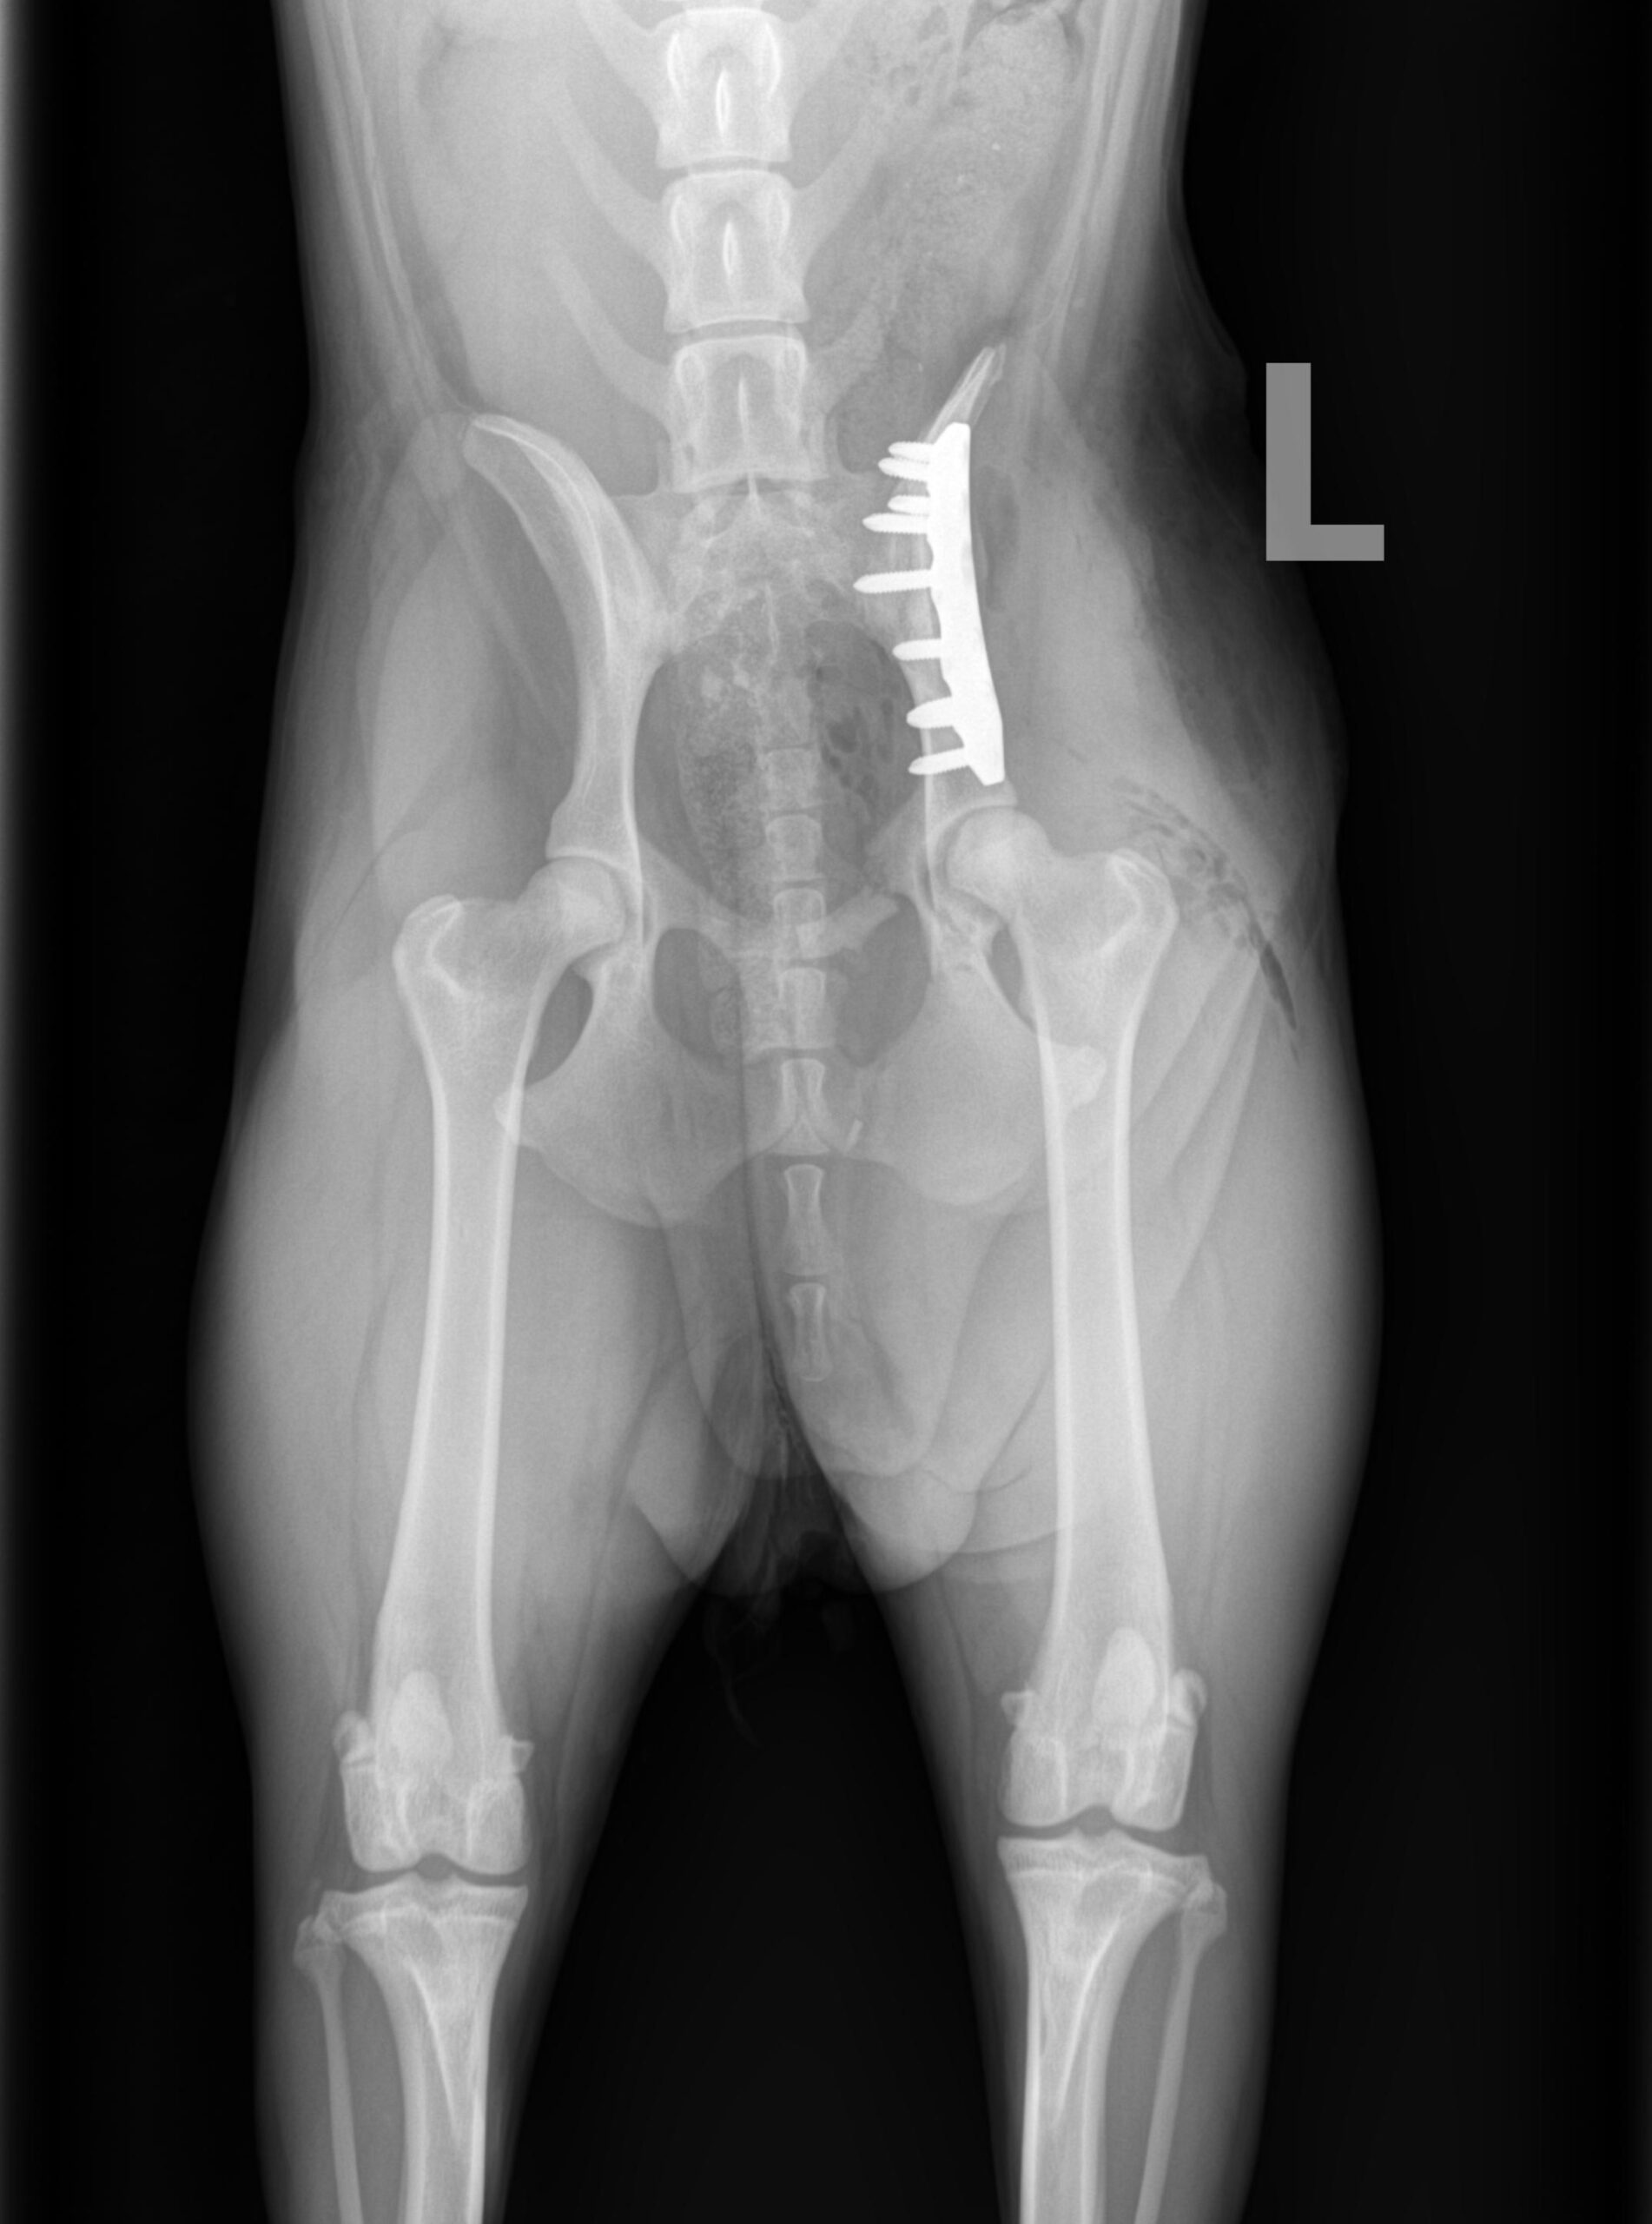

ADVANCED VETERINARY ORTHOPEDIC SERVICES

Our world-class, board-certified veterinary surgeons are dedicated to providing the most advanced canine orthopedic veterinary surgery and musculoskeletal assessment to ensure your beloved pet receives the most appropriate and comprehensive veterinary treatment available.